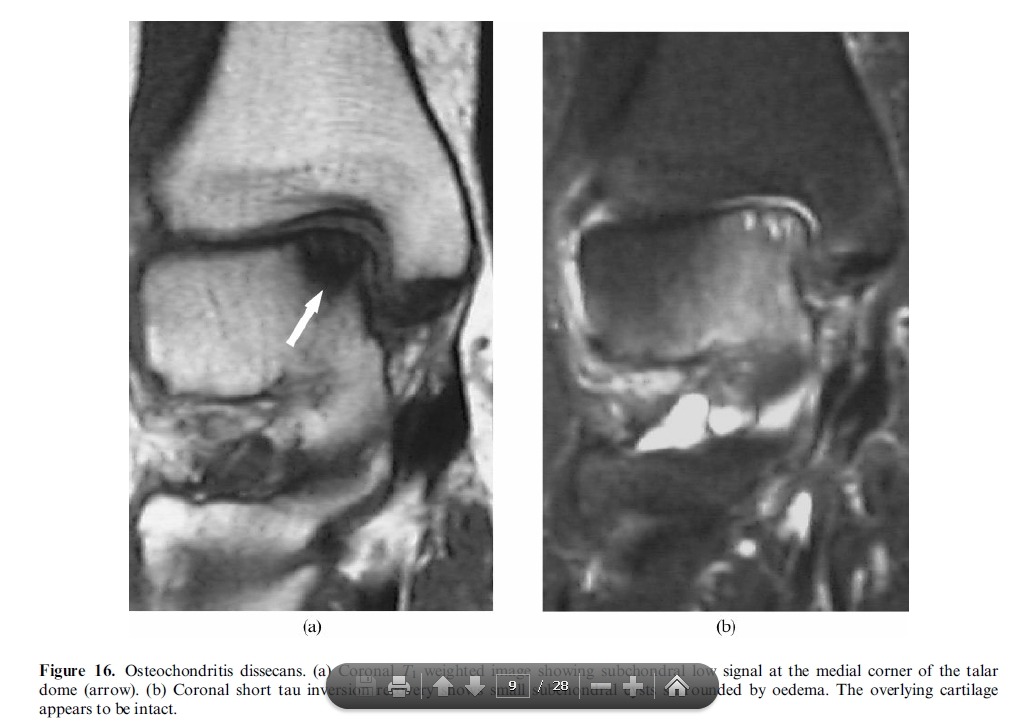

Trevor’s disease